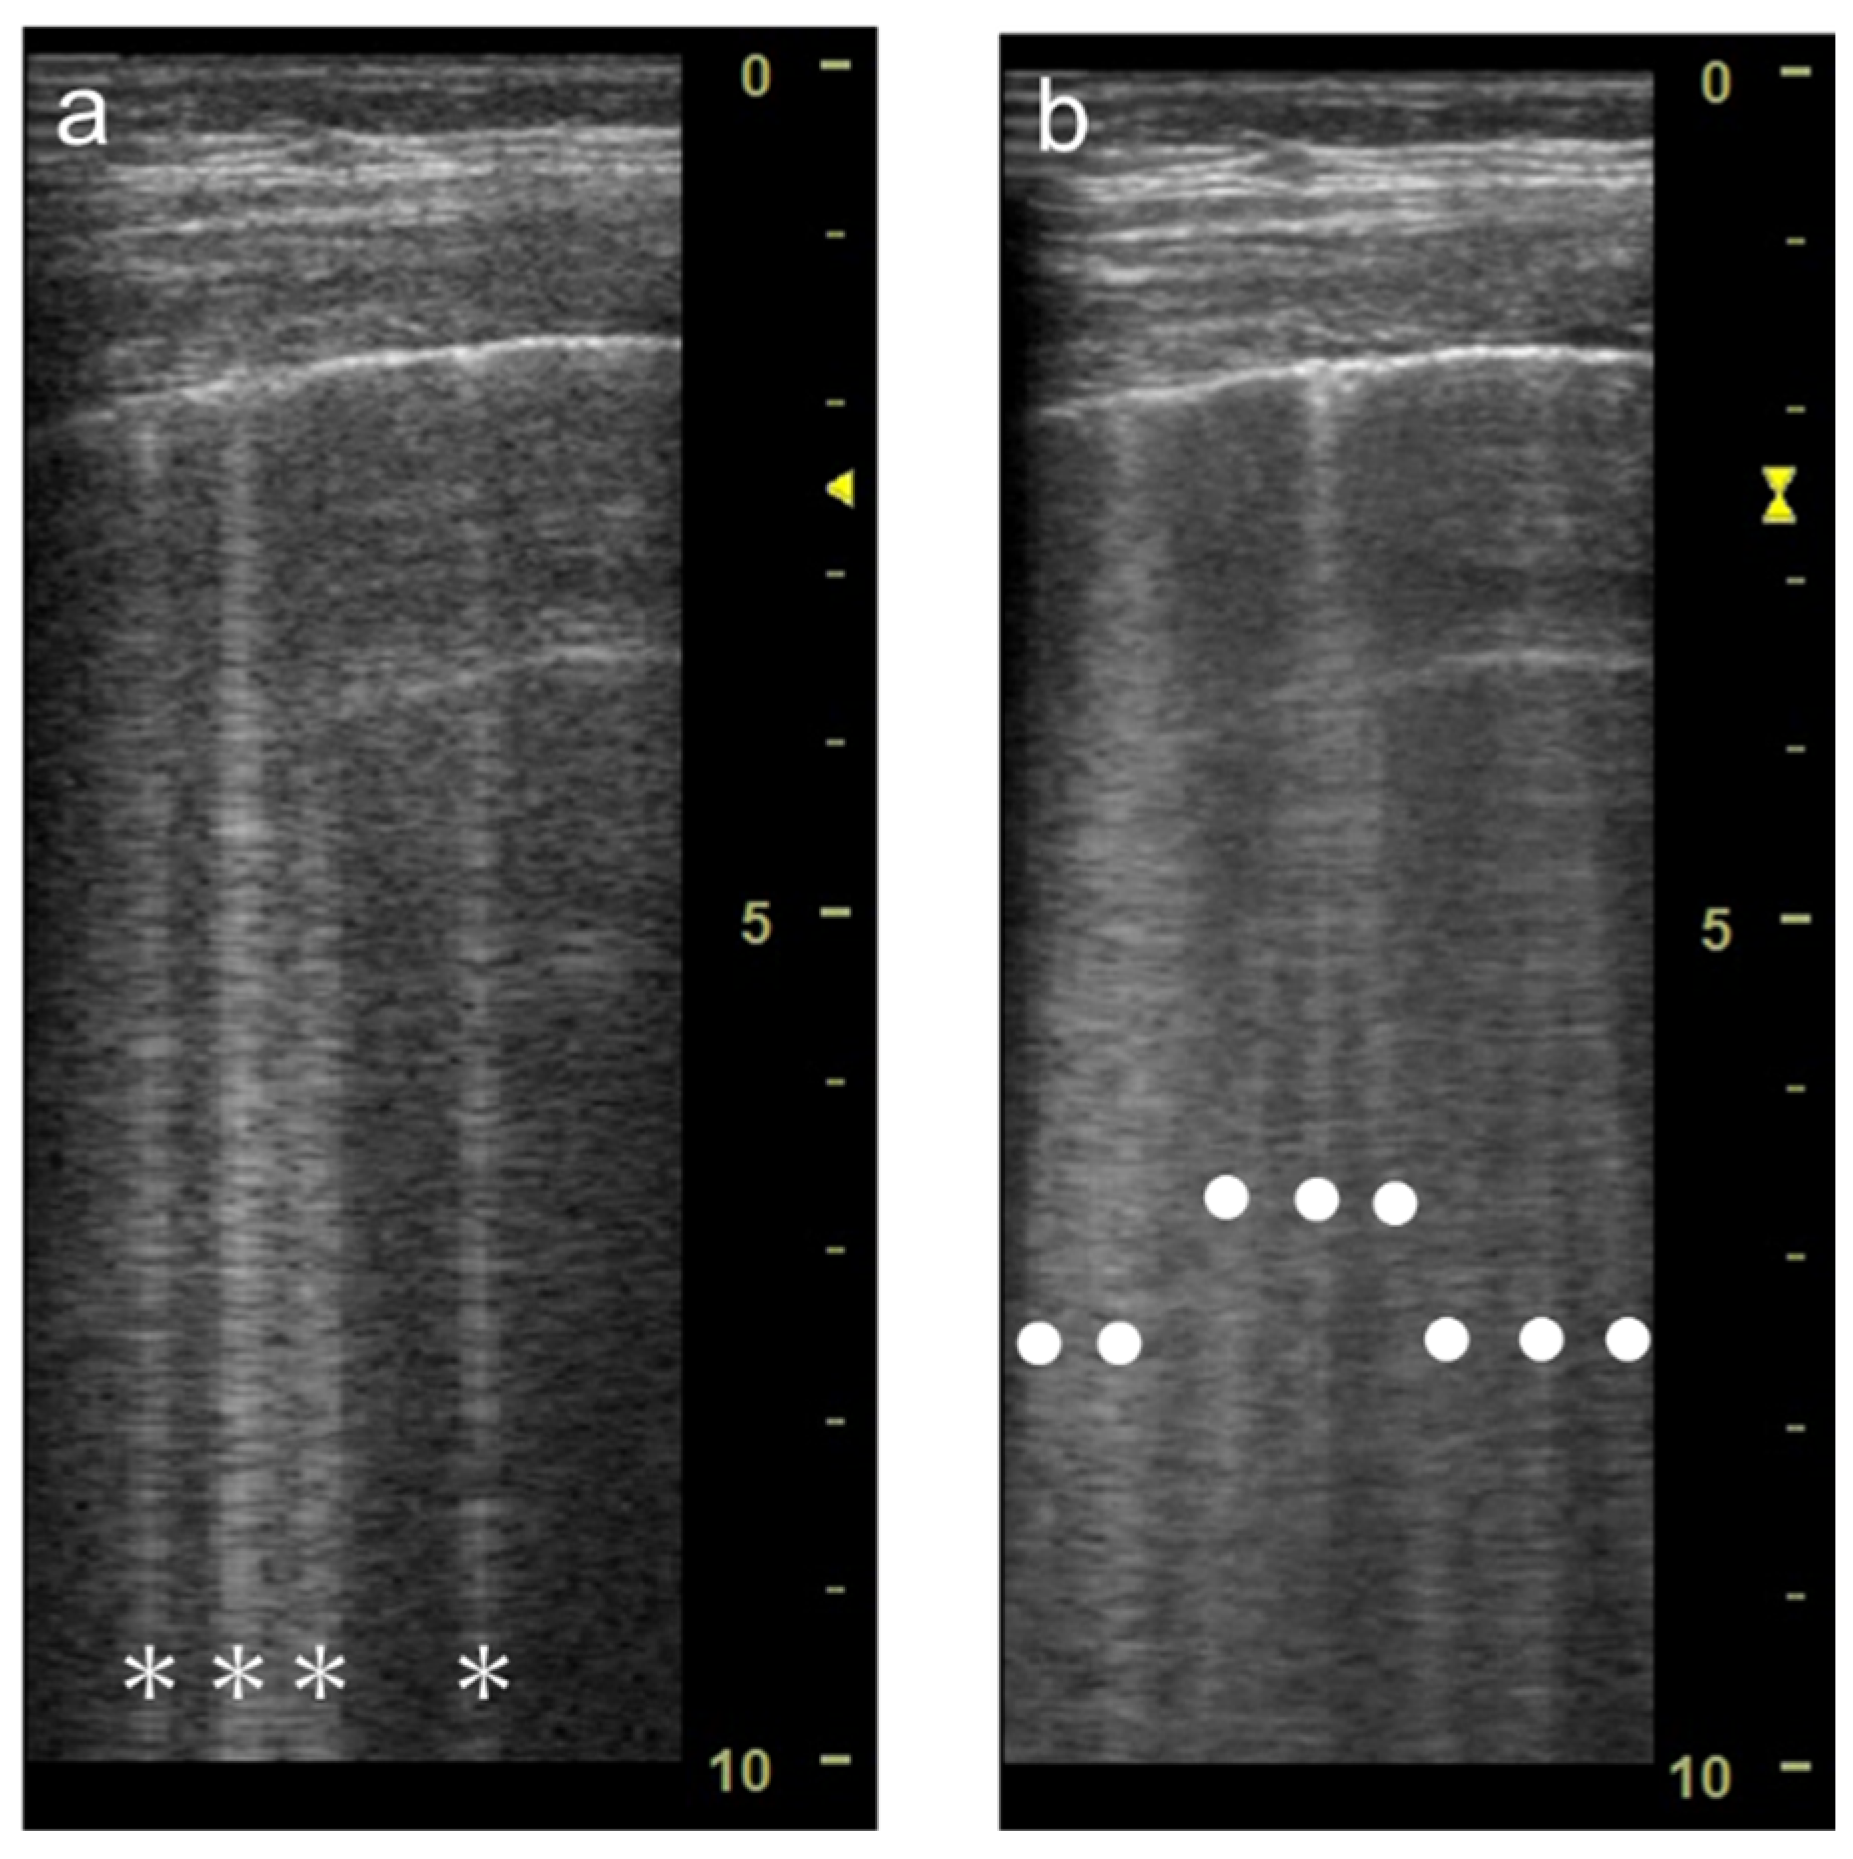

3.2. Focal Point